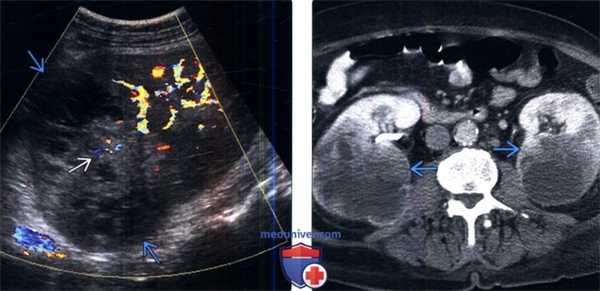

(Слева) Цветовое допплеровское картирование, сагиттальная плоскость: крупное гетерогенное объемное образование, замещающее верхний полюс правой почки (следствие метастатического немелкоклеточного рака легкого). Обратите внимание на внутренний цветовой поток в метастазах. Имеется аналогичного вида объемное образование в контрлатеральной почке (не показано).

(Справа) Последующая контрастная КТ, аксиальная проекция: у этого же пациента выявлены двусторонние гетерогенно окрашиваемые объемные образования почек с областями некроза (следствие метастатического немелкоклеточного рака легких).